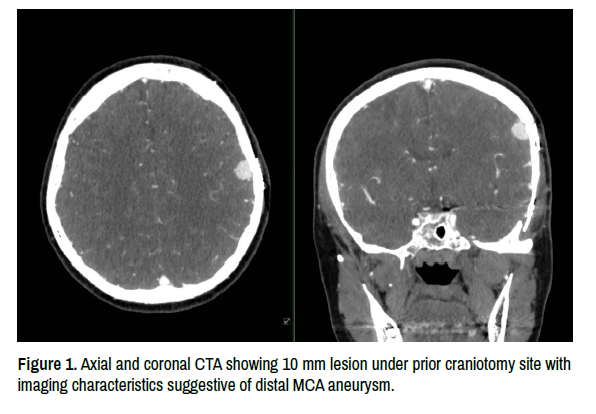

A 53-year-old woman with a history of breast cancer and an un-ruptured brain aneurysm was referred to our clinic to evaluate a possible new brain aneurysm. She underwent uncomplicated clipping of an un-ruptured left supraclinoid internal carotid artery (ICA) aneurysm nine years prior at a different institution and fully recovered. One year prior to the presentation, she began experiencing left-sided headaches that were worse in the mornings. Three weeks before the presentation, she was diagnosed with COVID infection and began experiencing vertigo. She underwent computed tomography angiography (CTA) that was interpreted as revealing a new 10 mm distal middle cerebral artery (MCA) aneurysm under her prior craniotomy flap (Figure 1). On neurological examination, she had a left frontal headache but no focal neurologic deficits. She denied any history of intravenous drug abuse or any other significant illness other than the COVID infection, from which she had recovered. Laboratory and other imaging tests were not informative.

Figure 1. Axial and coronal CTA showing 10 mm lesion under prior craniotomy site with imaging characteristics suggestive of distal MCA aneurysm.